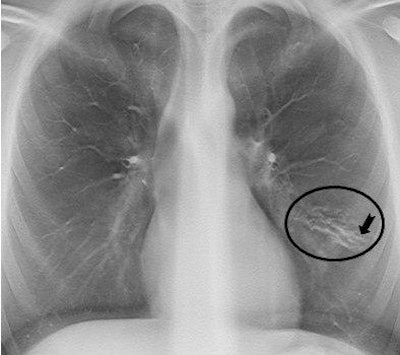

On a tomosynthesis section, cylindrical bronchiectases in the right upper lobe and small mucus plugs in a tree-in-bud pattern in the periphery of the lobe (arrows) are seen, but are not apparent on the AP radiograph. In the apical part of the left upper lobe, small cylindrical bronchiectases and mucus plugs (arrow) are seen.

On a tomosynthesis section, cylindrical bronchiectases in the right upper lobe and small mucus plugs in a tree-in-bud pattern in the periphery of the lobe (arrows) are seen, but are not apparent on the AP radiograph. In the apical part of the left upper lobe, small cylindrical bronchiectases and mucus plugs (arrow) are seen.While typical pulmonary changes in cystic fibrosis such as mucus plugging, bronchial wall thickening, and bronchiectases are superior in tomosynthesis images compared with a chest radiography, they are not superior to images produced by a CT scan. Depth resolution is inferior, and objects such as intravenous lines, tubes, or other devices generate artifacts within the area that is the most distant from the tomosynthesis sections. As a result, the lung parenchyma may be obscured. Localized air trapping and mosaic pattern cannot be adequately evaluated with tomosynthesis.

Another tomosynthesis section shows a slightly varicose bronchiectasis with severe wall thickening (circle) in the lingula segment of the left upper lobe. Small mucus plugs are seen in the area (arrow).

Another tomosynthesis section shows a slightly varicose bronchiectasis with severe wall thickening (circle) in the lingula segment of the left upper lobe. Small mucus plugs are seen in the area (arrow).Noting that their image analysis was limited to 145 examinations, the authors recommended that further evaluation of the role of tomosynthesis for monitoring disease progression in both adult and pediatric patients with cystic fibrosis should be undertaken.